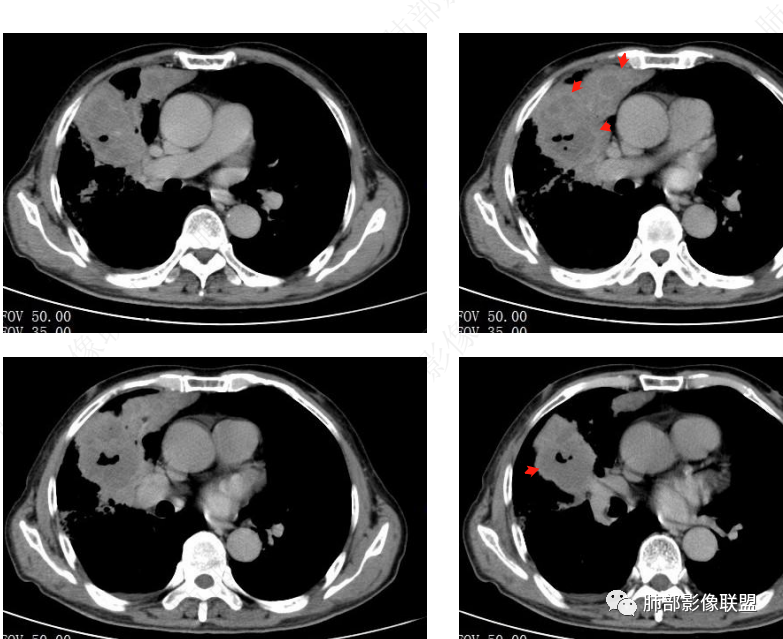

治疗前后对比CT:

放线菌病

八、影像特征:

1、慢性病程:慢性或亚急性化脓性肉芽肿性炎。

2、跨区域生长:放线菌不受解剖学屏障限制,可经胸膜进入胸腔或其他肺叶,可出现跨叶或累及胸膜、胸壁。

3、脓肿和坏死:局部扩散、多发脓肿、窦道形成,空气悬浮征。